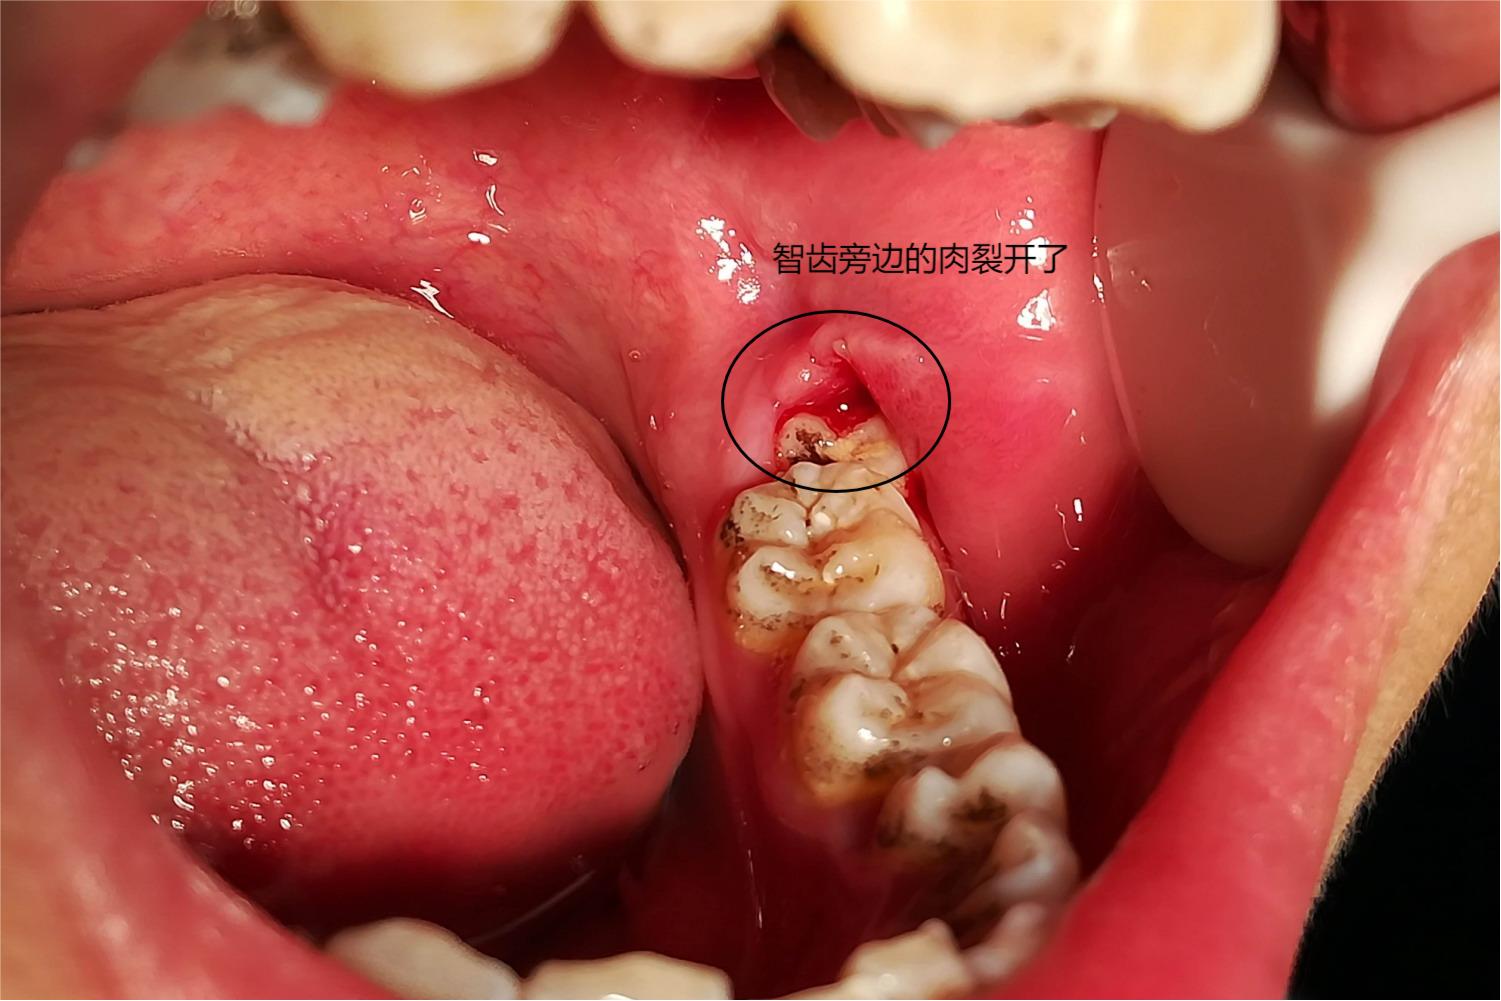

智齿旁边的肉裂开了图片

图片尺寸1501x1001